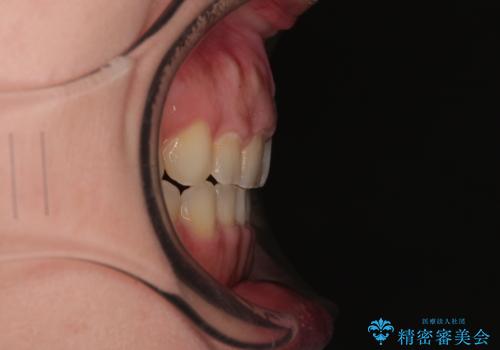

- 捻れて前に出ている上顎前歯と全体的なデコボコを気にして来院された患者様です。

口元の突出感は強くなかったため非抜歯矯正での対応となりますが、捻転を改善する際に上顎前歯が前突する可能性があったため、上顎臼歯部にアンカースクリューを使用して、歯列が前方に転位しないようにすることとしました。

ワイヤー矯正でもインビザラインでも対応可能でしたが、上顎歯列が前方位であるときには、ワイヤー矯正の方がより良い仕上がりとなる可能性が高いため、ワイヤー矯正をおすすめいたしました。